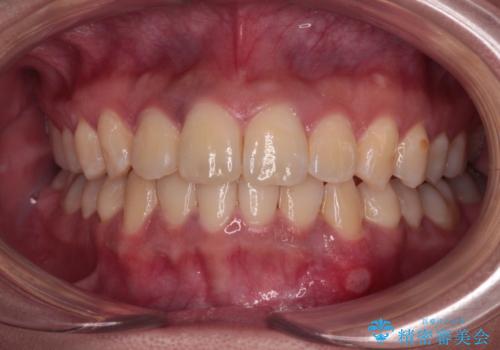

- 前歯のでこぼこと、やや口が閉じにくいことを気にして来院された患者様です。

上下左右の第一小臼歯4歯を抜歯し、歯列を整えながら第二大臼歯のクロスバイトを解除していくこととしました。

抜歯矯正での裏側装置特有の歯の傾斜を改善するために1年以上を要し、結果として3年半もの期間がかかってしまいました。

就職活動中や就職後も辛抱強く通院していただいたおかげで、患者様に満足いただける仕上がりとすることができました。